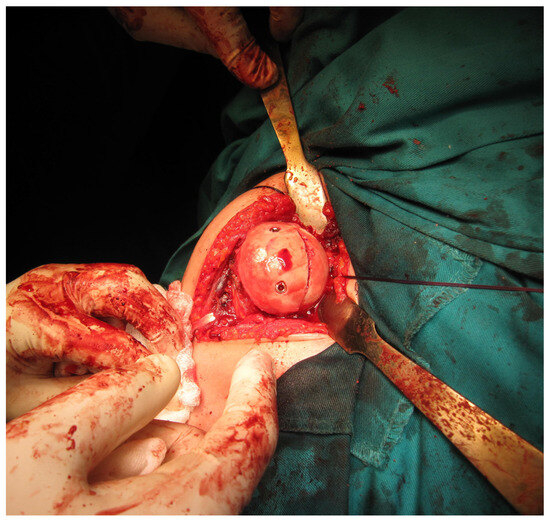

All examinees signed their informed consent. Patients underwent surgery at the Clinic for Orthopedic Surgery and Traumatology of the University Clinical Center of Vojvodina. Electrocution was the cause of injury in eight patients, direct trauma in ten patients and a fall due to hypoglycemic coma in two patients. There was no positive family history among the patients, and all injuries were unilateral. Eighteen patients had injured their dominant hand. Prior to the surgery, all patients underwent computed tomography (CT) scans to quantify the reverse Hill–Sachs lesions (Figure 1).

Following the confirmation of the diagnosis through traditional radiography, all patients underwent computed tomography (CT) scans. The dimensions of the defect in the humeral head were gauged using the preoperative CT scan while the head was dislocated posteriorly. A circular marker was placed over the humeral head in the CT scan taken at or just below the coracoid level. The cartilage angle was determined by two lines extending from the center of the circle to the cartilage immediately adjacent to the lesser tuberosity and the posterior end of the cartilage adjacent to the infraspinatus insertion. Another angle, referred to as the defect angle, was calculated by measuring the angles formed by connecting the anterior limit and posterior limit of the defect with the center of the humeral head. The size of the humeral head defect was estimated by determining what percentage of the cartilage angle the defect angle represented. A posterior glenoid rim defect that exceeded half of the maximum anteroposterior diameter was considered clinically significant.

Figure 1. Preoperative axial (A) and three-dimensional (B) CT image of a reverse Hill–Sachs lesion (photo from the personal archive of intraoperative photos of the author).